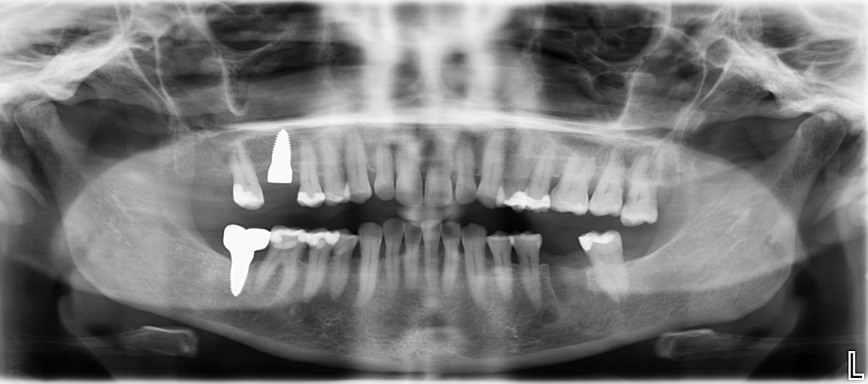

Die Implantat Entfernung in unserer Praxis

Bei der Implantat- Entfernung wird sehr genau gearbeitet, sodass keine Titanpartikel durch die Ausbohrung im Knochen zurückbleiben. Die Entfernung von Titanimplantaten erfordert nicht nur eine fachmännische chirurgische Technik, sondern auch eine umfassende Nachsorge (z.B. Schwermetallausleitung), um eine schnelle Genesung zu gewährleisten.

Unsere Praxis ist mit neuen Technologien und Materialien ausgestattet, um diesen Prozess so schonend wie möglich zu gestalten. In der Regel ist es möglich, die Titanimplantate aus dem Knochen herauszudrehen, ohne einen Knochendefekt zu hinterlassen.

Nach der Entfernung der Titanimplantate können bei gesundem Knochen Keramikimplantate sofort gesetzt werden. Mit dem unmittelbaren Austausch von Titan zu Keramik wird Zeit gewonnen, so kann das neue Implantat in dieselbe Stelle eingearbeitet und Knochenverlust vermieden werden.